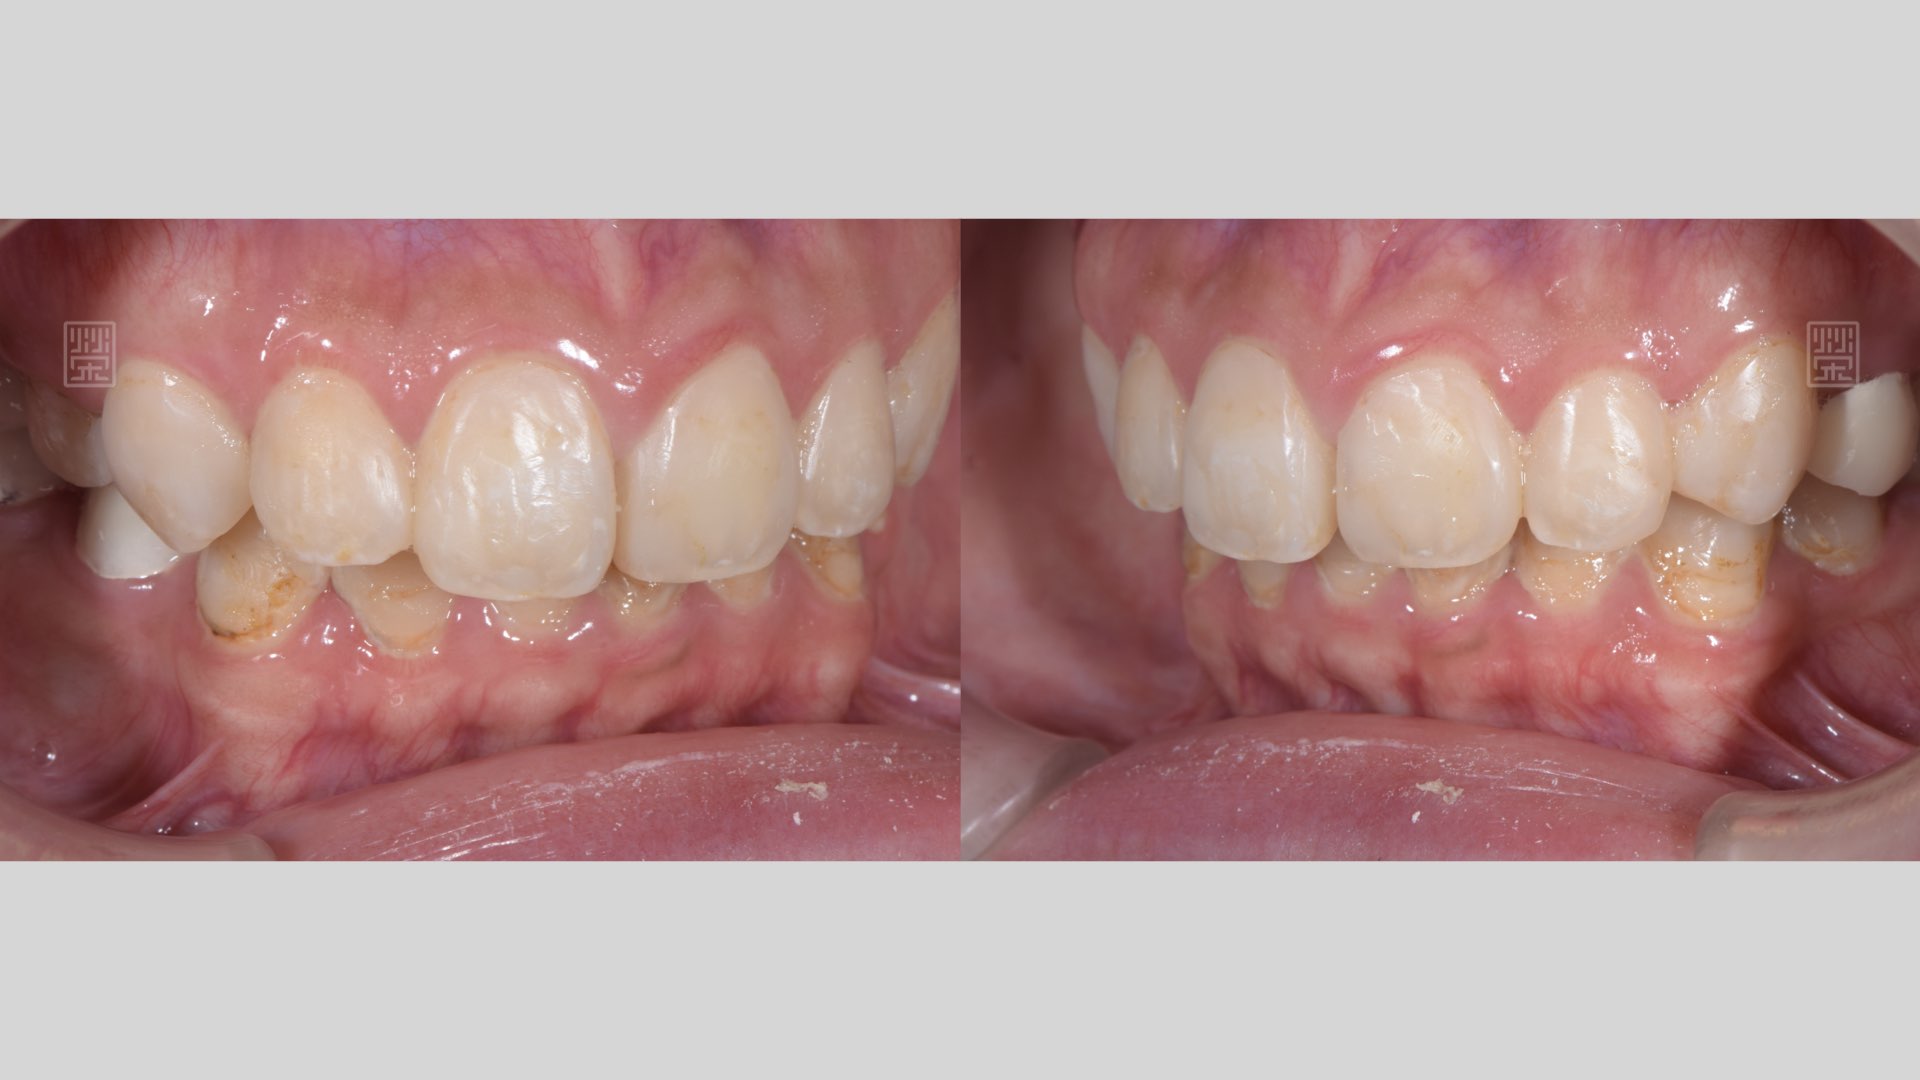

微笑曲線建立